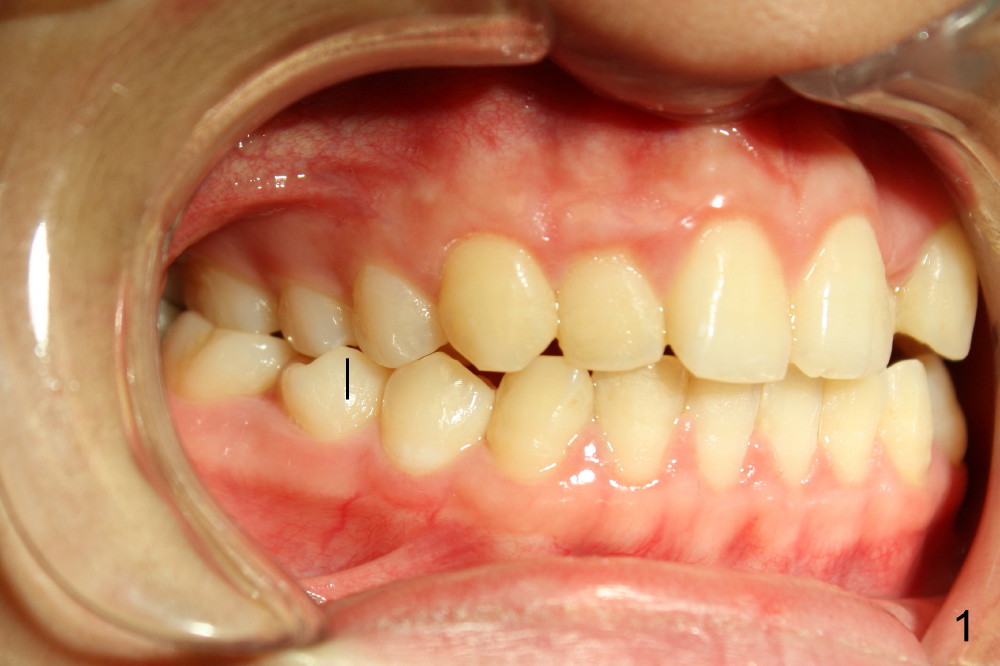

Ms. Xu, 16 years old, has bilateral posterior and UL 2 cross bite (Fig.1,2). L5s rotate (Fig.1-3: black lines).